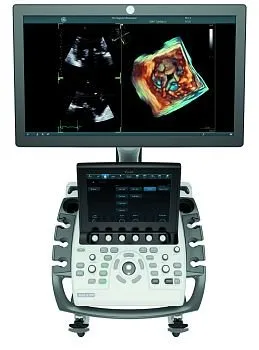

Экспертный LOGIQ P9 Версии R3 и R4 в наличии

Успейте приобрести по выгодной цене

Количество аппаратов ограничено